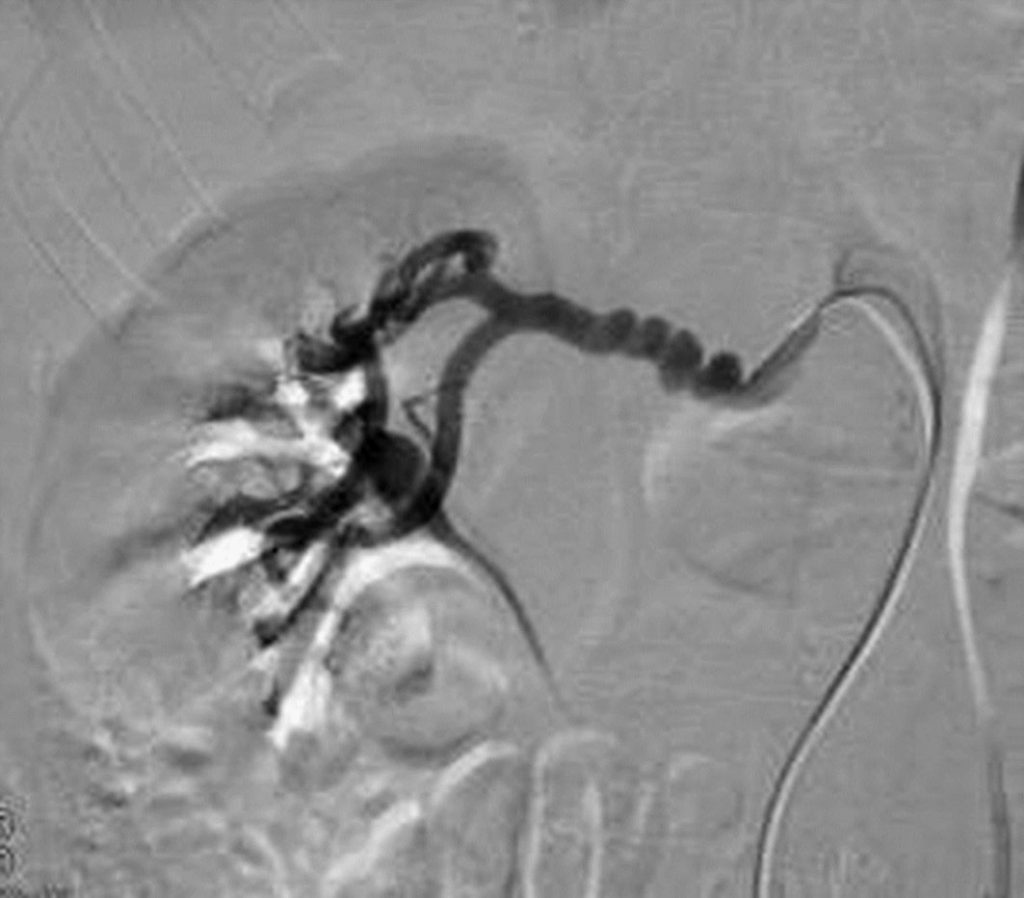

Les lésions de dysplasie fibromusculaire (figure 37.2) se caractérisent par des sténoses :

- tronculaires, à distance de l’ostium ;

- sous la forme de diaphragmes multiples ;

- séparées par des zones d’ectasies, donnant à l’ensemble un aspect en « chapelet » ou en « collier de perles ».

Fig. 37.2 Exemple d’artériographie montrant une sténose tronculaire dysplasique de l’artère rénale droite caractérisée par une succession de rétrécissements en diaphragme et d’ectasies à l’origine d’un aspect en « chapelet ».

Source : CERF, CNEBMN, 2022.